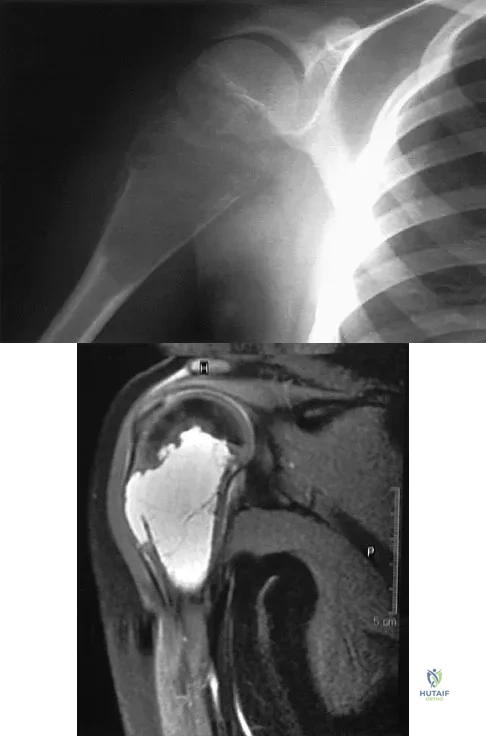

Question 35

An 11-year-old boy has right shoulder pain and has been unwilling to use the arm after throwing a baseball in a Little League game 3 weeks ago. Examination reveals upper arm and shoulder tenderness with swelling. A radiograph and MRI scan are shown in Figures 27a and 27b. Management should consist of